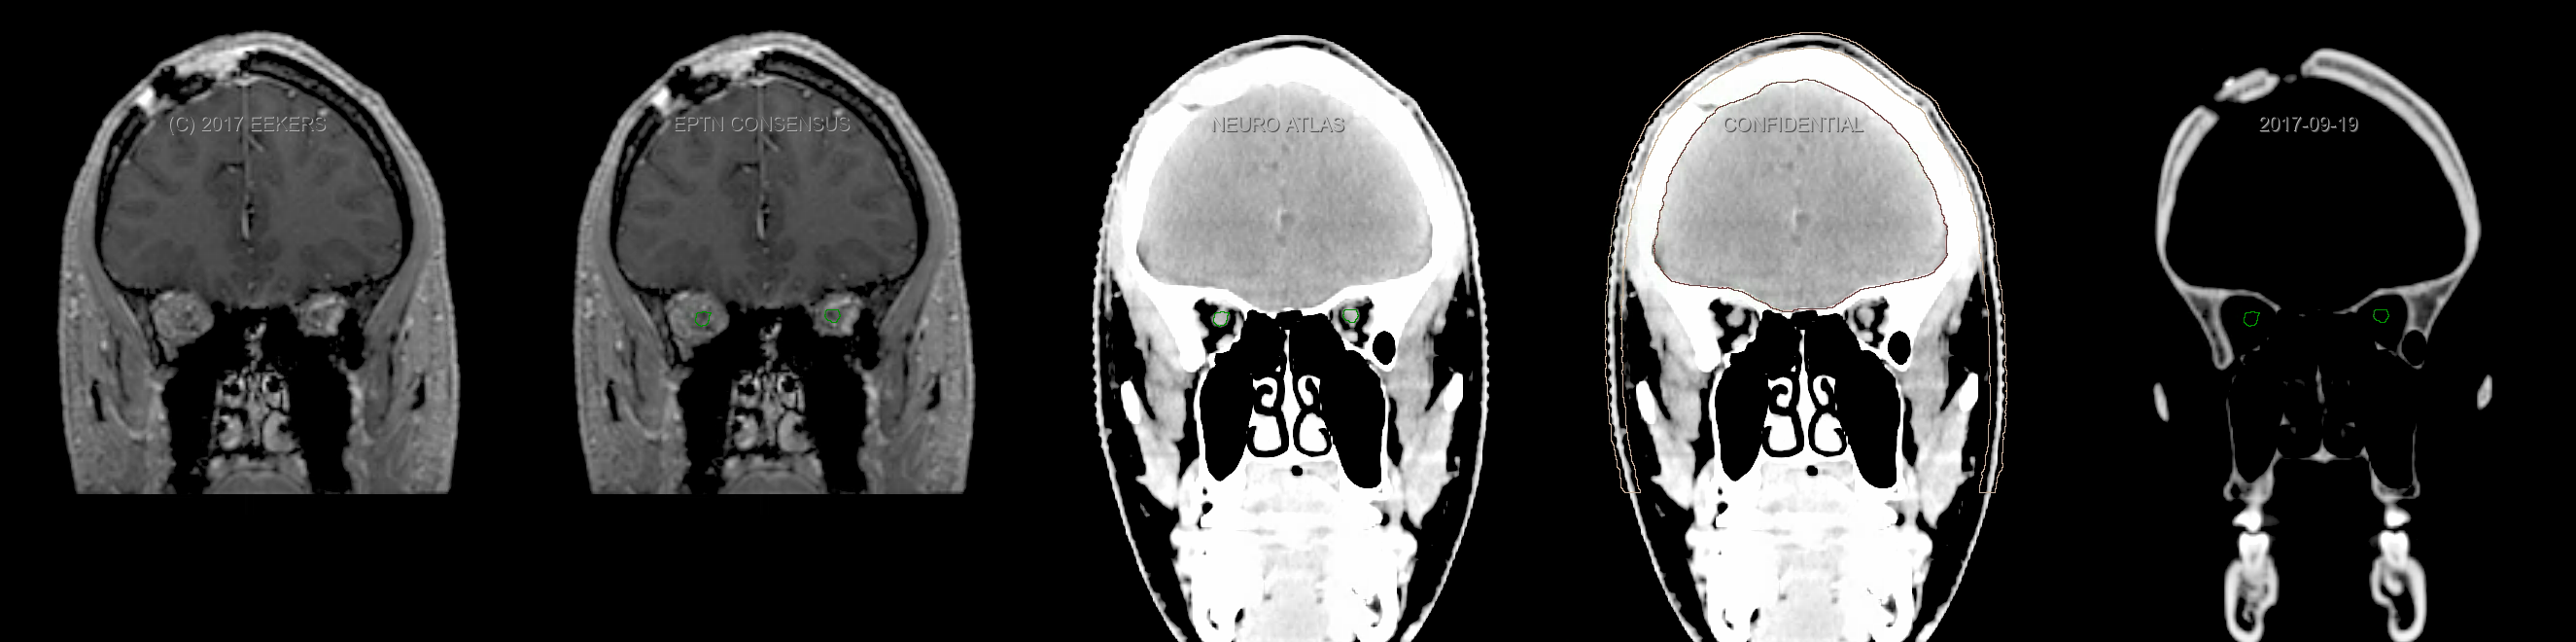

Eekers et al. have published an international neurological atlas for contouring of organs at risk in consensus with the European Particle Therapy Network (EPTN). The purpose of this consensus atlas is to decrease inter- and intra-observer variability in delineating OARs relevant for neuro-oncology. We propose this atlas is used in photon and particle therapy in order to derive consistent dosimetric data. When required this atlas will be updated according to new insights.

Included are all OARs known to be relevant for radiation-induced toxicity in neuro-oncology: brain, brainstem, cochlea, vestibulum & semicircular canals, cornea, lens, retina, lacrimal gland, optic nerve, chiasm, pituitary, hippocampus and skin. A new OAR relevant for neuro-cognition, the posterior cerebellum is also included.

Three-dimensional delineation of the fifteen consensus OARs for neuro-oncology are shown on CT and 3 Tesla (3T) MR images (slice thickness 1 mm with intravenous contrast agent). All are presented in transversal, sagittal and coronal view.

From left to right: MR without structures, MR with structures, CT (WW/WL 120/40) with structures, CT (WW/WL 120/40) with Brain and Brainstem Surface, CT (WW/WL 1500/120)with structures